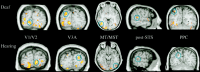

Fig. 3.

Example of activations in motion-related areas for one deaf and one hearing participant.